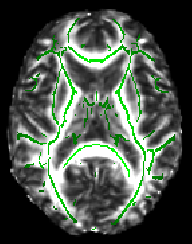

cd stats fslview all_FA -b 0,0.8 mean_FA_skeleton -b 0.2,0.8 -l Green

The -b option sets sensible display range options, and in the case of the skeleton image, also controls the thresholding applied. Now turn on the movie loop; you will see the mean FA skeleton on top of each different subject's aligned FA image. If all the processing so far has worked ok the skeleton should look like the examples shown here (see the TBSS paper for more examples of different subjects' results underneath the skeleton). If the registration has worked well you should see that in general each subject's major tracts are reasonably well aligned to the relevant parts of the skeleton. If you set the skeleton threshold (in FSLView, the lower of the display range settings) much lower than 0.2, it will extend away towards extremes where there is too much cross-subject variability and where the nonlinear registration has not been able to attain good alignments. Remember the skeleton threshold for the next stage.